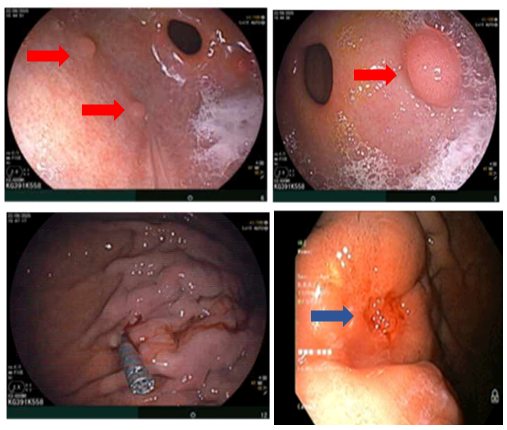

- Nội soi dạ dày: Thân phình vị, thân vị có đám niêm mạc co kéo, hội tụ, lõm ở trung tâm kích thước~ 3.0cm, bề mặt niêm mạc biến đổi

Hình 2

. Hình ảnh các polyp ở dạ dày (mũi tên đỏ). Niêm mạc dạ dày co kéo, lõm ở trung tâm (mũi tên xanh)

- Nội soi đại tràng: Phần quan sát được: Dọc đại tràng có nhiều polyp, tập trung ở đại tràng sigma kích thước ~ 0.3 - 0.6 cm. Trực tràng có nhiều polyp kích thước ~ 03-0.6 cm.

Hình 3

. Hình ảnh các polyp rải rác ở đại tràng (mũi tên đỏ)